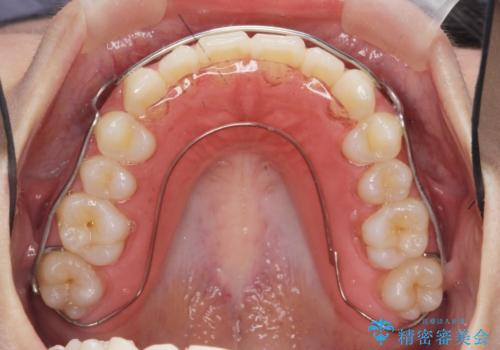

ガタつきの改善 マウスピース矯正治療

- 歯のがたつきの改善を求めて、矯正治療を希望され来院されました。

少量の歯のディスキング、歯列弓拡大、アタッチメントを装着することで審美的な歯列へとマウスピース矯正インビザラインを用いて治療を行います。

マウスピース矯正は装着時間の遵守が非常に大切ですが、しっかりと20時間/日以上の装着を守っていただいたおかげで良好な治療結果を得ることができました。